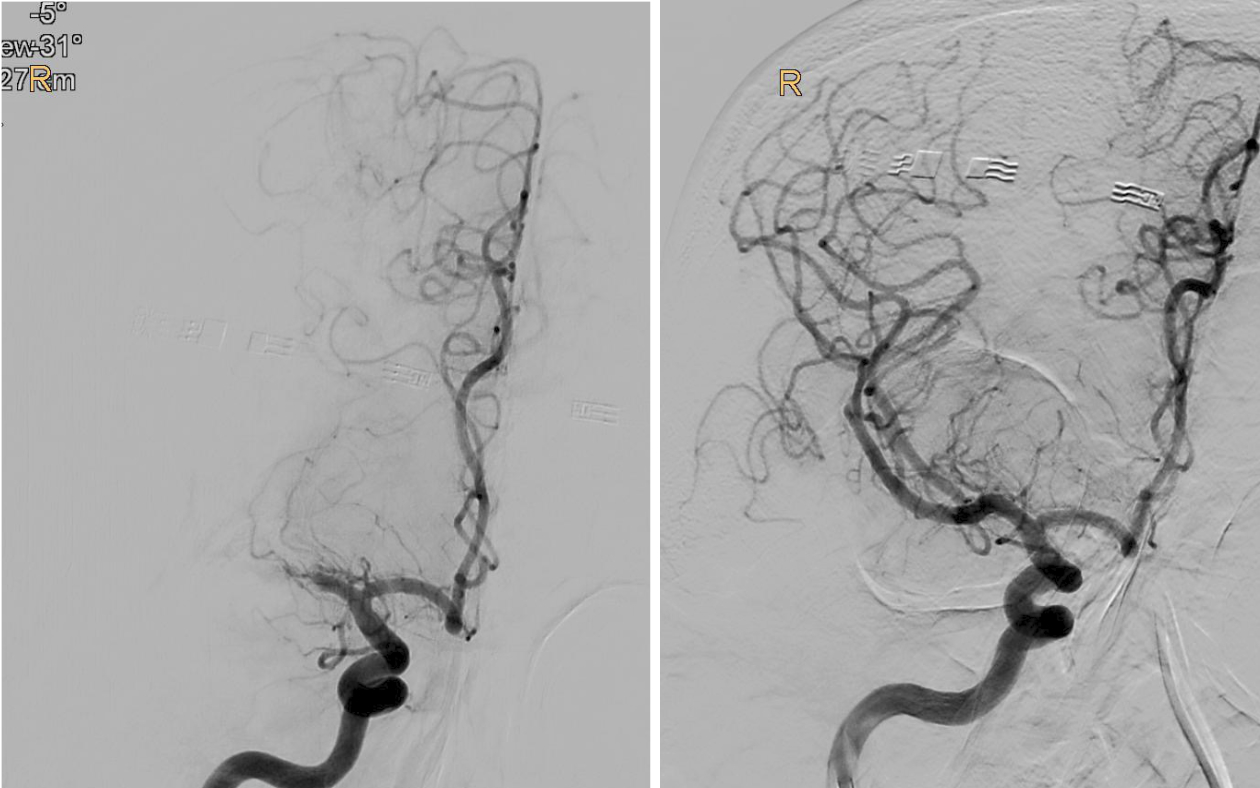

BU: Verschluss des mittleren Hirngefäßes in der Angiographie dargestellt (l.), und wieder eröffnet (r.). Bilder: Univ.-Klinik für Radiologie

„Bei einem Schlaganfall zählen einerseits Zeit und andererseits die noch verbliebene Sauerstoffversorgung des Gehirns, welche bei den Patient:innen unterschiedlich ausfällt. So genannte Kollaterale, Gefäß-Querverbindungen, können die Durchblutung noch einige Zeit aufrechterhalten. Je weniger solcher Kollateralen vorhanden sind, desto weniger Zeit hat man. Doch auch wenn schon Gewebe untergegangen ist, kann man noch etwas retten, wenn man thrombektomiert. Das konnten wir jetzt mit der TENSION-Studie zeigen“, berichtet Gizewski. Viele der Patient:innen könnten trotz der bedrohlichen Ausgangssituation jetzt wieder ein eigenständiges Leben führen. Nachdem sich der Erfolg der Katheter-Behandlung (insgesamt 125 Patient:innen) in der randomisierten Studie im Vergleich zur besten konservativen medizinischen Behandlung (128 Patient:innen) schnell gezeigt hatte, wurde die Studie frühzeitig beendet.